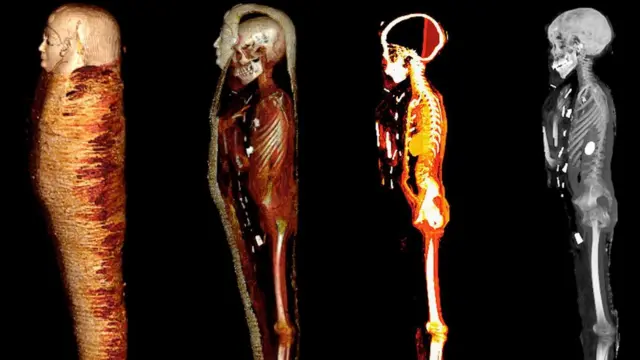

У мумії "золотого хлопчика", яку знайшли в Єгипті ще в 1916 році, вчені за допомогою комп'ютерної томографії виявили золоте серце, язик і безліч амулетів.

Коли команда вчених на чолі з докторкою Сахар Салім з Каїрського університету вирішила вивчити цю мумію за допомогою комп'ютерної томографії (їхня робота опублікована у виданні Frontiers in Medicine), дослідники були вражені, коли виявили на знімках у мумії - золоте серце, золотий язик, і загорнуті разом із нею в саван 49 амулетів, багато з яких теж зроблені з золота. Вчені негайно охрестили мумію "Золотим хлопчиком", і після закінчення робіт її перенесуть до головної зали музею.

Знімки також показали, що під бинтами, якими було обгорнуто тіло покійного в процесі муміфікації, ховаються численні амулети 21 виду, до рота йому помістили золотий язик, а до грудної клітки - золотого жука-скарабея у формі серця.

Мумія "золотого хлопчика" була запечатана у двох саркофагах. На зовнішньому був напис грецькою, внутрішня частина саркофага була виконана з дерева, а саму мумію прикрашала золота маска.